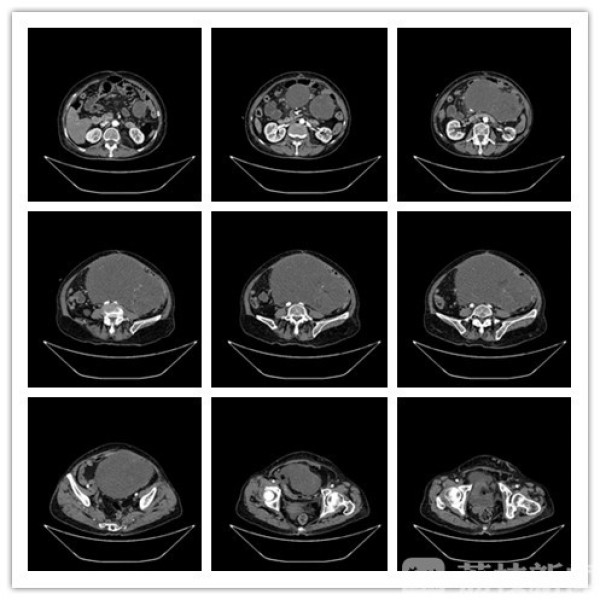

84岁的患者尹女士2个多月前出现腹痛腹胀,CT检查发现腹部巨大占位,收住鼓楼医院江北国际医院普外科病区。专家团队考虑到尹女士腹部的肿瘤巨大——直径超过25cm,如果不手术,就不会有任何生活质量,而且生命也随时受到威胁。

术中,尽管尹女士腹部被切开了30多厘米的创面,但医生的视野还是被巨大肿瘤全部占据,无法判断肿瘤的起源位置。为尽量保证肿瘤的完整性,管文贤主任决定将附着在肿瘤表面的肠管分离开来,现场再次仔细“阅片”,发现肿瘤的主要供血血管位于左上腹,依据丰富的临床经验,果断决定断掉该处血管,减少术中出血。经过近4个小时的细致操作,一个重达10余斤的腹腔肿瘤终于被完整切除。